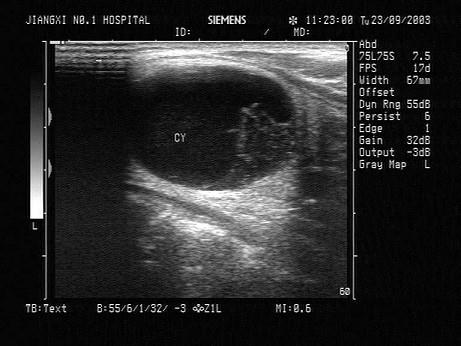

问题 患者,男性,甲状腺一侧可触及包块,超声见边界清晰的低回声光团,包膜完整。如图所示,最可能的诊断为?(?)

选项 A.甲状腺腺瘤并囊性变 B.甲状腺炎 C.结节性甲状腺肿 D.甲状腺癌 E.甲状腺囊肿

答案 A